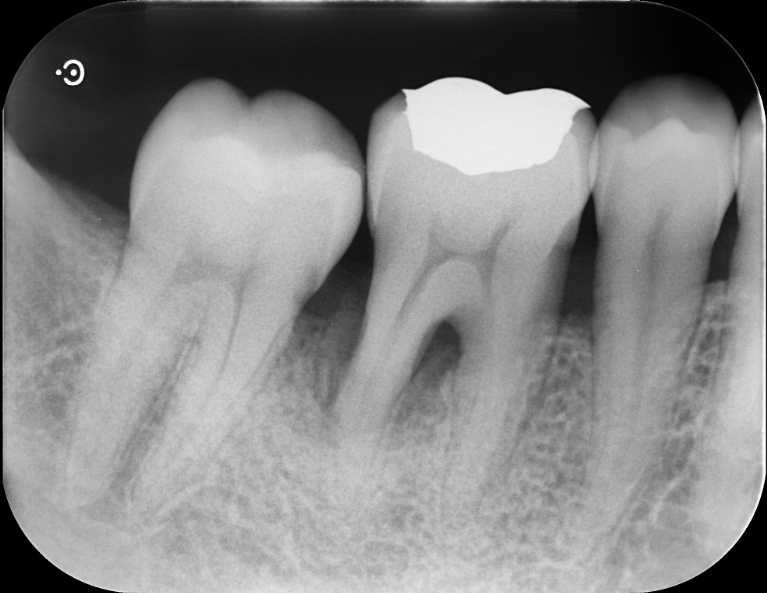

Case2

術前

術中

術後

| 治療名 | 再生療法 |

|---|---|

| 治療説明 | 右下6に重度の歯周病があり、通常の歯周治療でも改善しませんでした。歯周組織再生療法を行い、吸収してしまった骨を再生し、今後の歯周病の進行リスクを減らす事ができました。歯肉退縮もあったため同時に結合組織を移植し、骨と歯肉の再生を同時に行っています。 |

| 治療回数・期間 | 6ヶ月 |

| 副作用とリスク | 手術後に出血、腫脹、疼痛が生じることがあります。手術後は術部の創傷安定のためにブラッシング制限、食事制限があります。手術が複数回となることがあります。 |

| 料金(税込) | 再生療法:165,000円 結合組織移植:55,000円 総額:220,000円 |